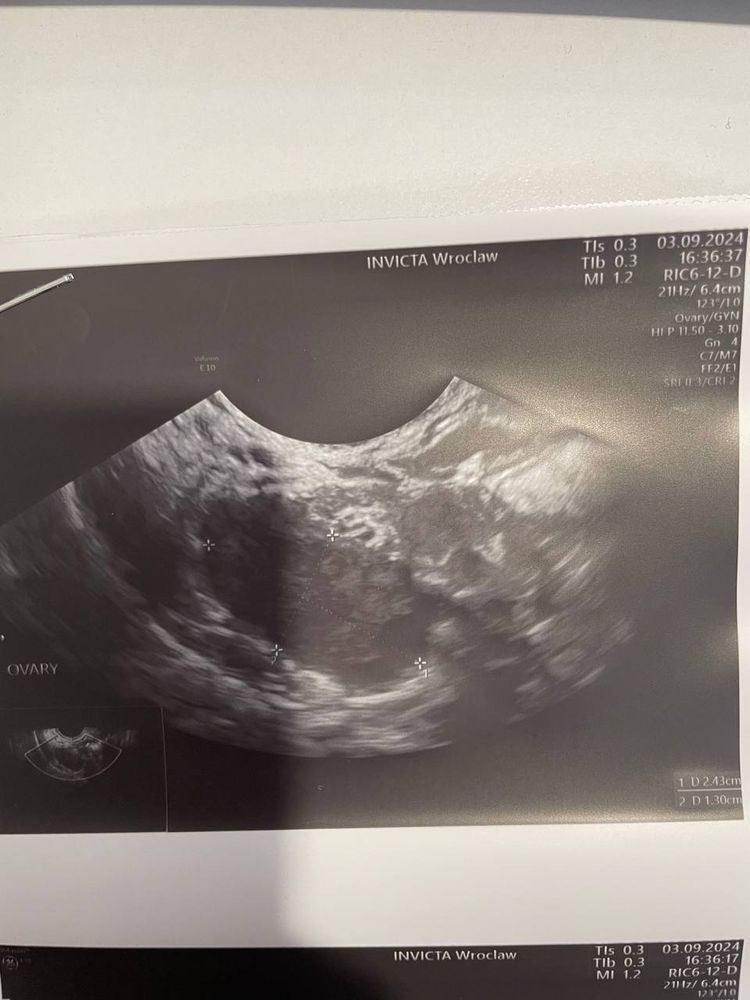

А на третьем скорее всего доминантный фолликул и яичник)

Ну на правом яичнике видно какие то черные пятна, похожи на фолликулы. На левом вот это одно большое, непонятно какого размера, может фолликул, может киста с прошлого цикла. И мелкие черные пятна если приглядеться по краю яичника - это фолликулы